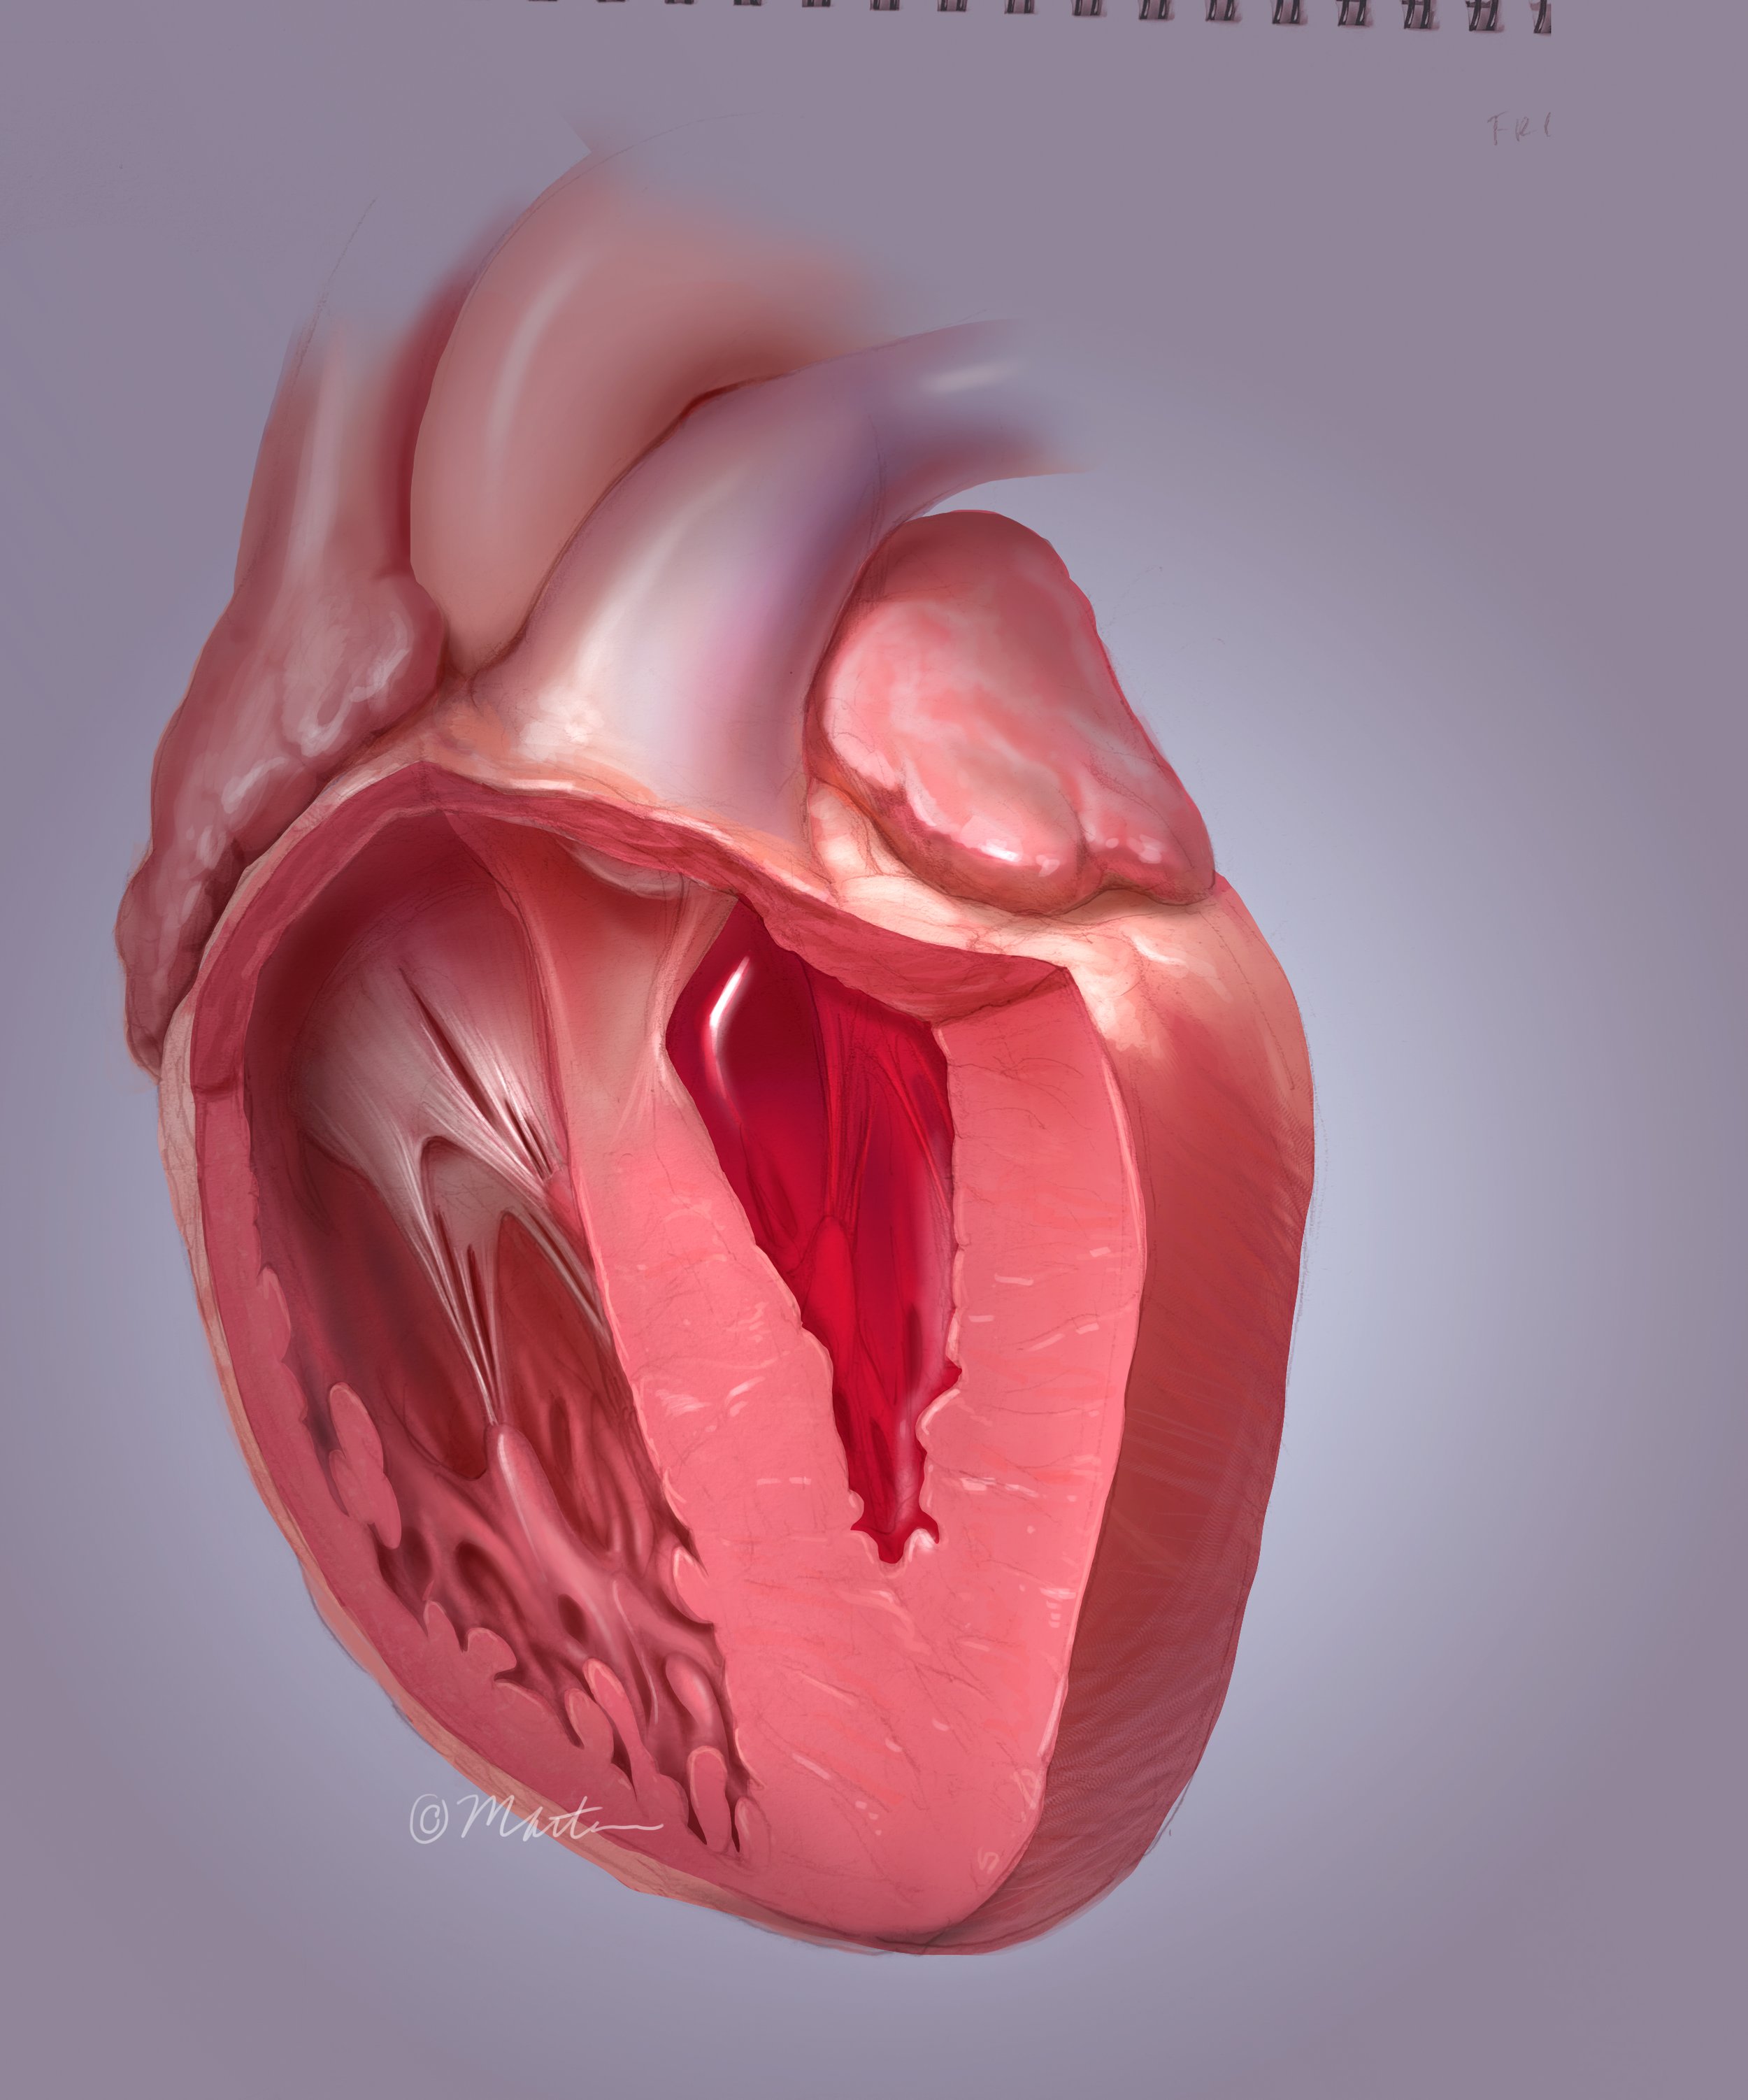

Diastolic Heart Failure